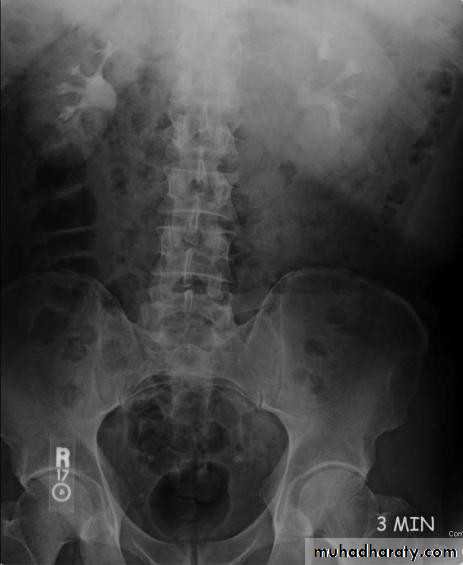

• Intravenous (Excretory) Urography

• 5 minutes

• Check the Kidneys: outline, size, site

• Check the calyces: cupped• Check renal pelvis and ureter

• Check the bladder